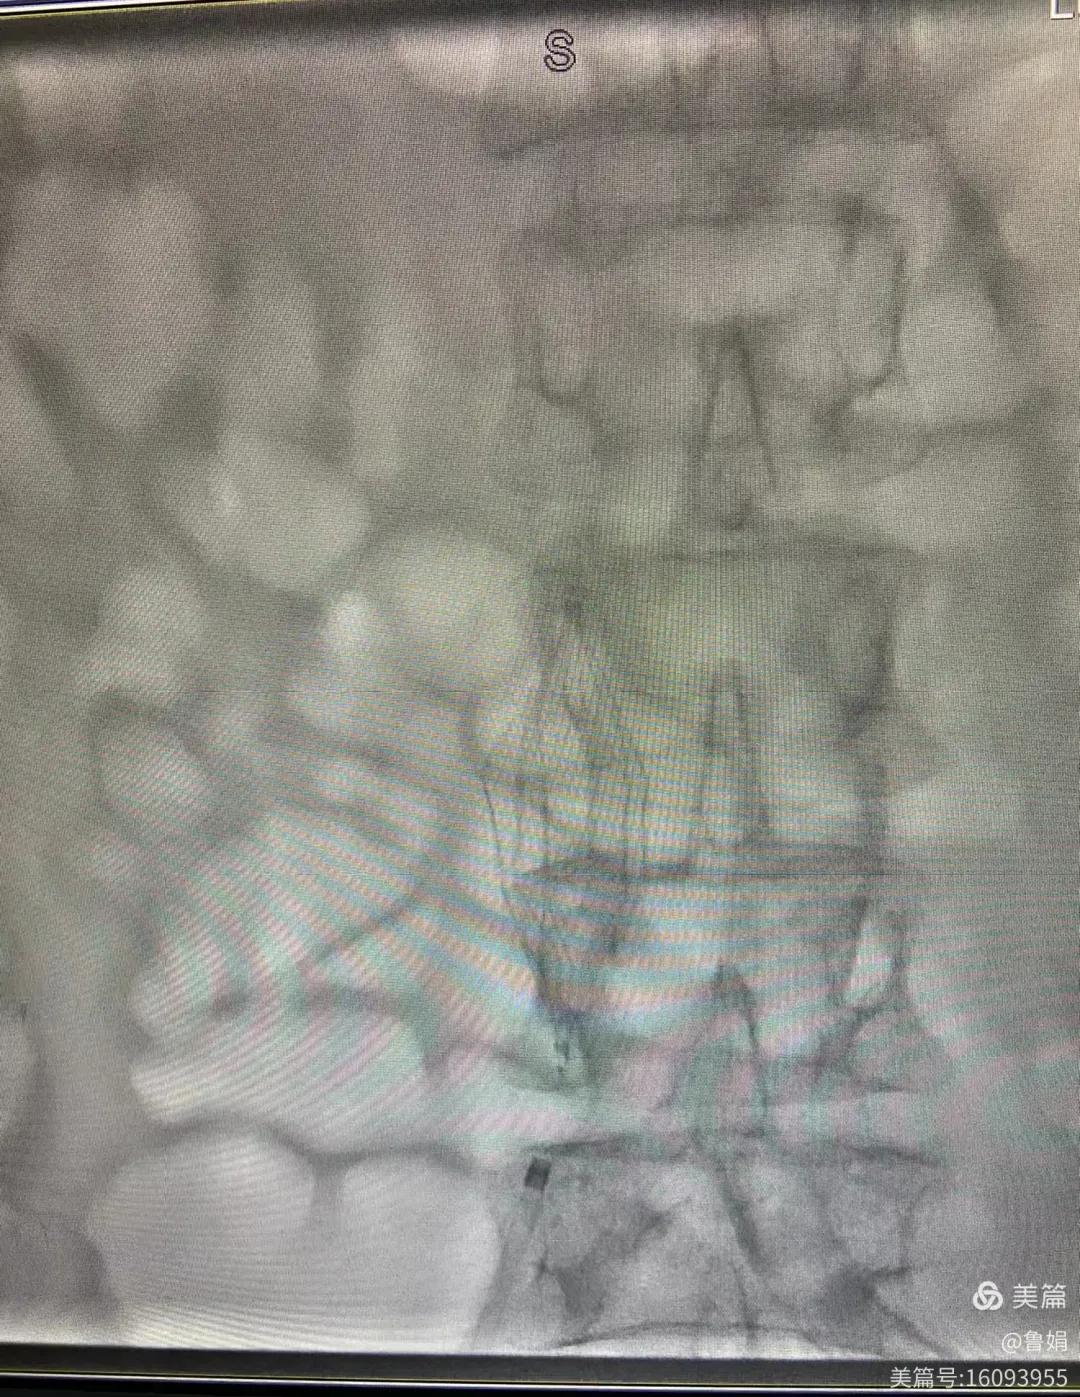

11月3日,漯河市中醫(yī)院血管外科副主任周創(chuàng)業(yè)與腦二科介入醫(yī)生孫亞中,兩位醫(yī)生為一位腦梗死伴下肢深靜脈血栓形成患者成功開展下腔靜脈濾器置入術。

圖片術后濾器順利植入

經(jīng)認真查看患者病例,探討患者病情及術中潛在風險因素,多科會診后急診為患者開展介入手術,術中周創(chuàng)業(yè)副主任、孫亞中副主任中醫(yī)師二人通力合作,手術順利,病人術中出血少,生命體征平穩(wěn),現(xiàn)在腦二科病房繼續(xù)對癥治療。(介入中心:魯娟)